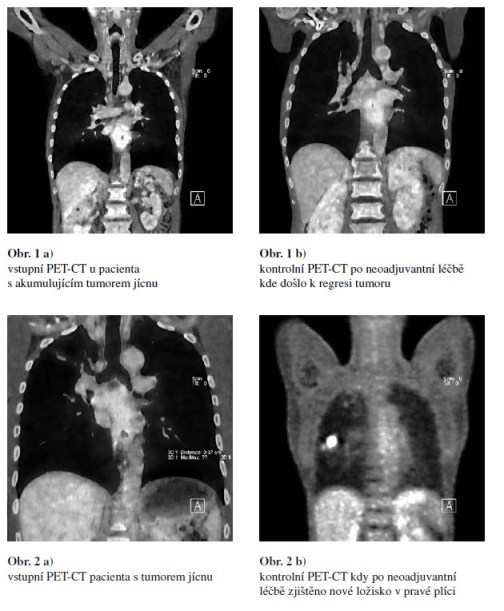

U všech 140 pacientů po ukončení neoadjuvantní onkologické léčby bylo provedeno kontrolní PET-CT, které mělo za úkol vyloučit progresi onemocnění a porovnat velikost a charakter současného tumoru se vstupním PET-CT. U 121 pacientů ukázalo kontrolní PET-CT regresi onemocnění (Obr. 1). Radikální chirurgický výkon byl provedený u 78 z těchto pacientů, u zbývajících 43 z důvodu celkově zhoršeného zdravotního stavu či nepříznivé lokalizaci nádoru byla chirurgická léčba kontraindikovaná. U 19 pacientů s progresí onemocnění na kontrolním PET-CT bylo ustoupeno od radikálního operačního výkonu, tito pacienti byli léčeni pouze paliativně (Obr. 2).